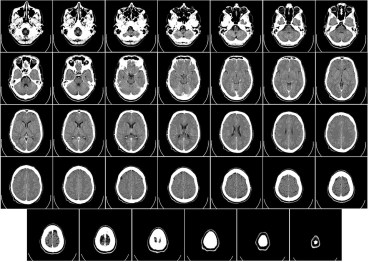

A 2010 study tested this concept in a group of radiologists. The physicians were shown brain CT scans of a group of patients who presented with ischemic stroke. The radiologists were told to interpret the images without a medical history or any subsequent diagnostic studies. They were specifically asked to estimate the chances an acute stroke was present and, if so, to identify the location of the stroke.

After a washout period, the studies were shuffled and shown to the same radiologists again. This time, however, they were told the presenting symptoms and given a follow-up MRI to read. How do you think they did? The radiologists were, of course, far better at finding strokes on CT scans when they had additional information and knew the outcome of a follow-up MRI.

But before you dismiss that as an obvious outcome, ask yourself how this scenario is any different than a clinician comparing the judgment of a colleague to his own judgment an hour, or a day, or a week later. The passage of time inevitably yields additional information that, in turn, increases the likelihood of a “good decision.”